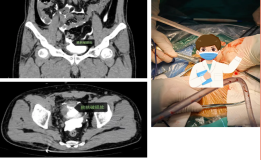

勇闯生命禁区,心脊双关创奇迹——我院疼痛脊柱科成功为77岁心脏瓣膜病患者完成高难度UBE镜下融合内固定手术

中西医协同破解老年脊柱侧弯难题,我院脊柱外科成功开展高难度开放融合手术